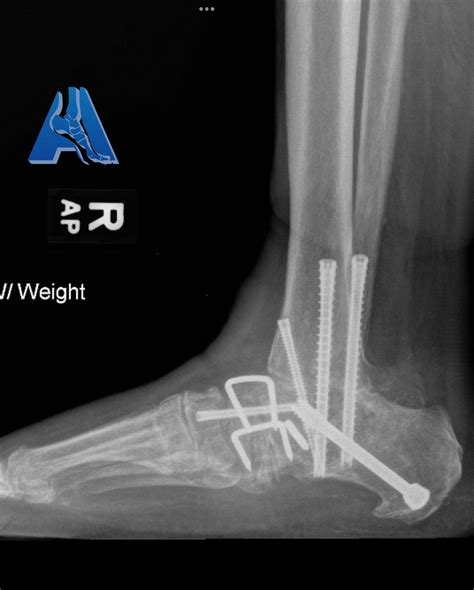

• Fixation: The bones are aligned and held in place using screws, plates, or rods. These fixation devices provide stability while the bones heal and fuse together.

• Hardware Failure: The screws, plates, or rods used to hold the bones in place can break or loosen, requiring additional surgery.